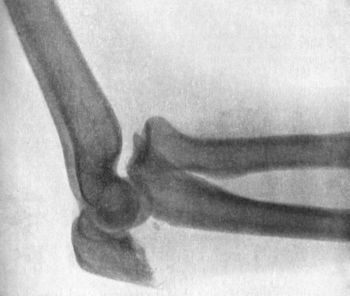

36.Backward Dislocation of Elbow in a Boy89

38.Radiogram of Incomplete Backward Dislocation of Elbow91